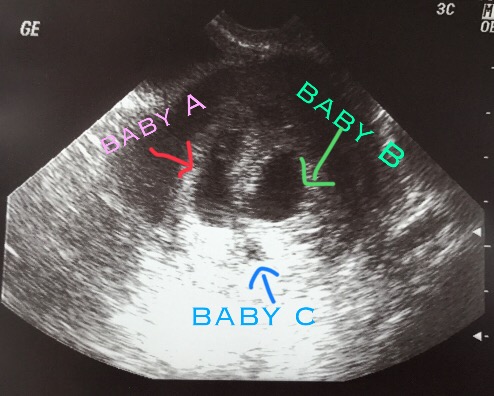

At six weeks, we had our first ultrasound. When the image pulled up on the screen Dr. S. immediately says, “that’s why you are so sick. There are three babies!” I honestly don’t know what mine or Joe’s reactions were because we were both in shock. Dr. S. was hesitant though because Baby C was much smaller than the other two and said it would most likely “peter out”. Joe and I were like okay, it looks like we are having twins then and we were still so happy.

A few days later I experienced some bleeding and was terrified. I called Dr. S. and she said it was normal and try not to worry about it because it had already stopped and was most likely from the third baby. She wanted to see me again at seven weeks because it was triplets and to check on Baby C. My seven week ultrasound showed that Baby A and Baby B were right on track and it showed Baby C was still growing and it had a heartbeat. Dr. S was still concerned because it was significantly smaller than baby A and Baby B though. This meant we had graduated from the fertility clinic and we were referred to the San Diego Perinatal Center to see a perinalogist.

Joe and I continued to tell ourselves it was most likely going to be twins still and tried not to worry about Baby C. When my perinatologist told us that all three babies looked healthy we both gave a huge sigh of relief. I didn’t realize how worried and hopeful I was about Baby C until we found out that it was doing fine. This is when it started to sink in that we were having three babies! We were going to have to figure out how to take care of TRIPLETS and buy everything in threes. We felt that God had blessed us with these three miracles and he would take care of us.